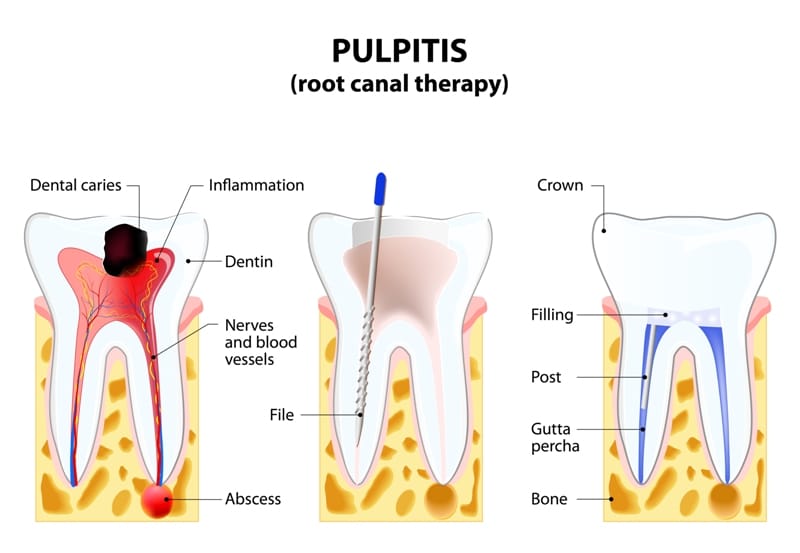

A dental crown is a cap placed over a damaged tooth to restore its shape, size, and function. However, the crown protects the outside of the tooth, while the living tissue inside, known as the pulp, can still be vulnerable. The pulp contains nerves and blood vessels that nourish the tooth. If it becomes infected or inflamed, a root canal is required to save the tooth.

Once the pulp is accessed, the dentist will carefully remove the infected or inflamed tissue. Using specialized instruments, they will clean, disinfect, and shape the inside of the root canals. This step is crucial for eliminating all bacteria and preventing future infection.

After the canals are thoroughly cleaned, they are filled with a biocompatible, rubber-like material called gutta-percha. This material seals the canals to prevent bacteria from re-entering. The small opening in your crown is then closed with a temporary filling to protect the tooth until a permanent restoration is placed.

At a follow-up visit, the temporary filling is removed. If the existing crown is still in good condition and fits properly, your dentist may place a permanent filling in the access hole. If the crown was damaged or needs to be replaced for a better seal, a new one will be created and cemented into place.